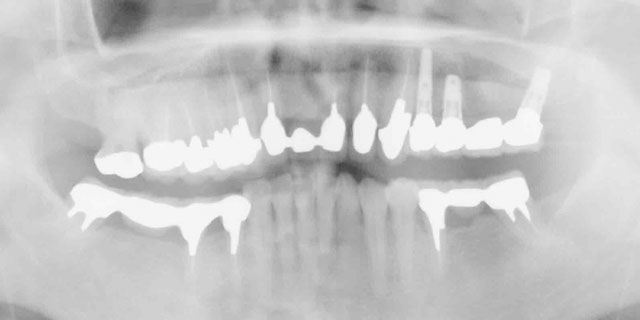

治療開始時

4本の歯で入れ歯を支えていましたが、歯根が割れてしまいました。割れた歯根は抜歯しなくてはいけません。抜歯後は歯が一本もない状態になります。

4本のご自身の歯が残っています。残った歯にバネを掛けて義歯を使用していましたが根が割れて歯の周りが化膿しています。

治療中

抜歯後にインプラントを埋入して固定式のブリッジを作ります。このケースでは6本のインプラントを使用しました。

フルブリッジをインプラントに固定して治療終了です。ほとんど自分の歯と同じに使用できます。

治療終了

インプラントとブリッジをセメントで固定しました。